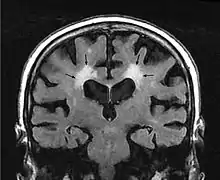

El término leucoaraiosis se utiliza en medicina para describir un hallazgo radiológico que consiste en la pérdida difusa de densidad en varias regiones de la sustancia blanca del cerebro, próximas a los ventrículos cerebrales y a la corteza cerebral profunda.[1] No es un diagnóstico, sino un hallazgo radiológico, se detecta mediante imágenes obtenidas por diferentes técnicas, como la resonancia magnética nuclear y la tomografía axial computarizada.[2]

En la Tomografía Computarizada, la leucoaraiosis se observa como regiones con menor densidad, mas oscuras que las circundantes, es decir áreas hipodensas, en Imagen por Resonancia Magnética se define como lesiones con mayor intensidad de señal es decir áreas hiperintensas, por presentar un aspecto más brillante que las zonas aledañas. Estas imágenes pueden verse en las regiones próximas a los ventrículos cerebrales, corona radiata y centro semioval.[9] Se han utilizado escalas cualitativas como la de Fazekas para determinar el grado de las lesiones:

- Grado 0 corresponde a ausencia de lesión.

- Grado 1 lesiones focales.

- Grado 2 lesiones confluentes iniciales.

- Grado 3 cuando las lesiones difusas son muy extensas y comprenden regiones cerebrales completas.